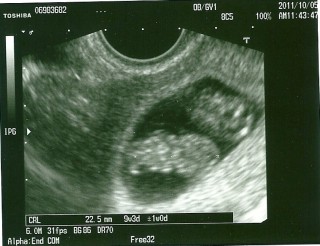

赤ちゃんの大きさ25ミリ、心臓もしっかり動いており、順調だと言われました。

排卵日確定しており、週数に誤差はありません。

ちっちゃなおててとあんよも見えました♪右が頭です…頭でっかちかわいい